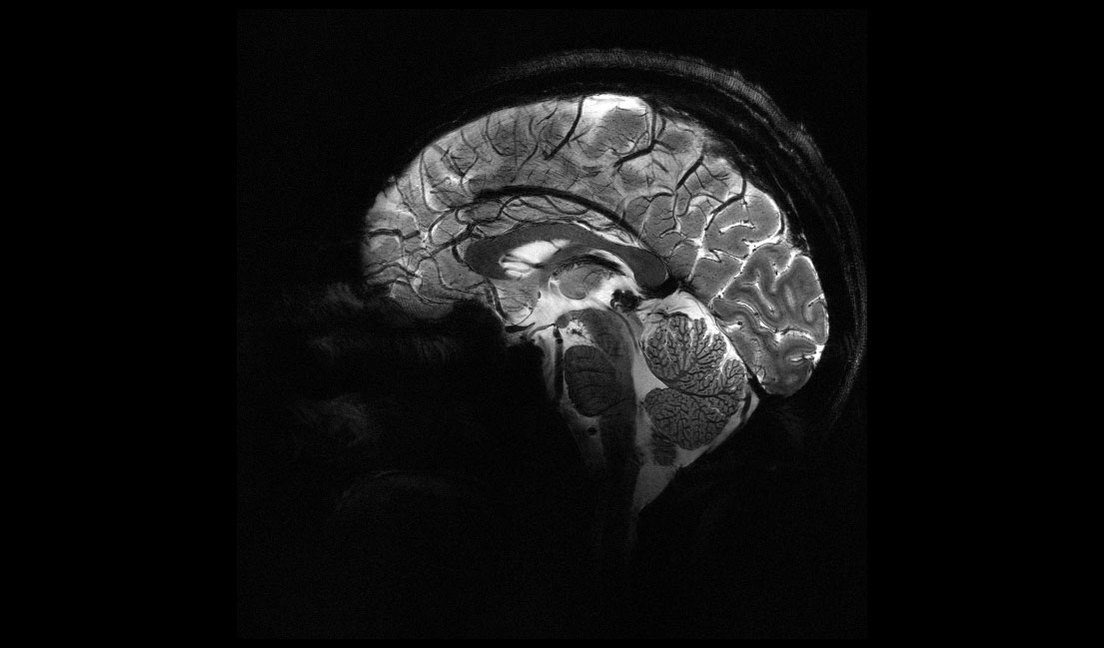

En un estreno mundial, los investigadores de la Comisión de Energía Atómica (CEA) de Francia revelaron este martes una serie de imágenes 'in vivo' del cerebro humano, adquiridas con la máquina de resonancia magnética más poderosa del mundo. La Iseult, que cuenta con un inigualable campo magnético de 11,7 teslas y fue construida en un esfuerzo de dos décadas, ha captado el cerebro vivo con una claridad sin precedentes.

Las más notables imágenes anatómicas del cerebro nunca antes obtenidas se tomaron en apenas cuatro minutos. Los expertos señalan que su resolución es impresionante para un lapso temporal de adquisición tan corto. Se logró una resolución en el plano de 0,2 mm y grosor de corte de 1 mm, lo que representa un volumen equivalente a unos pocos miles de neuronas.

En comparación, la misma calidad de imagen requeriría horas con los escáneres de resonancia magnética actualmente disponibles (de 1,5 o 3 teslas). Esto no es realista en la práctica, ya que los pacientes no se sentirían cómodos y cualquier movimiento haría que la imagen se vea "borrosa".